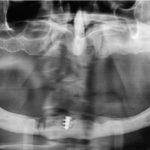

Gli autori descrivono un caso clinico di grave malocclusione a seguito di trauma mandibolare trattato in altra sede. Il piano di trattamento ha previsto...